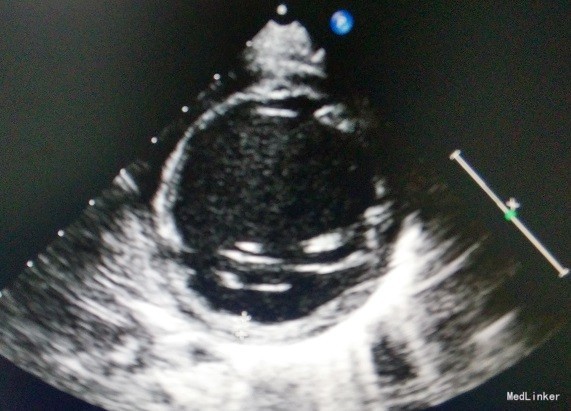

主诉:男,5月15天,发现心脏增大2周 病史:入院前2周,患儿因“神萎、纳差半月,加重2天”于当地医院行心脏B超示:“左室显著扩大,左室心内膜非均匀增厚,左心功能降低,左室射血分数33%”心电图示:”窦性心动过速,部分ST-T改变“,胸片示:”左肺大片高密度影,肺部感染或胸腔积液“诊断为”心力衰竭,心内膜弹力纤维增生症?婴儿肺炎“予以头孢噻肟、强心、利尿等治疗9天后,患儿精神,食纳好转出院,出院后继续口服地高辛、卡托普利、螺内酯、氢氯噻嗪治疗,现患儿为求进一步诊疗,遂来我院,门诊以”心内膜弹力纤维增生症“收住我科,起病以来患儿汗多,余无异常。

心内膜弹力纤维增生症是指心内膜弥漫性的弹力纤维增生性疾病。可伴有心肌退行性变。心脏的四个心腔都可单独或联合受累,但以左室为多。临床上分暴发型、急性型及慢性型,主要表现为充血性心力衰竭,暴发型可表现为心源性休克。暴发型及急性型多于生后6个月内发病,慢性型多于6到12个月内发病,相当一部分患儿尤其是慢性型的心衰对毛地黄效应好,如及时诊治,可获全愈,否则常危及患儿生命。本病无明显地区性。国内报道男性发病多于女性。本病的特征为:①1岁以内婴儿多数于2~6月时突然出现心力衰竭;②X线胸片心脏扩大以左室为主,心搏减弱;③心脏无明显杂音;④心电图表现为左室肥厚,或V5、6导联T波倒置。⑤超声心动图表现为左室扩大,心内膜回声增粗,收缩功能降低。组织学上确诊须行心内膜心肌活栓。